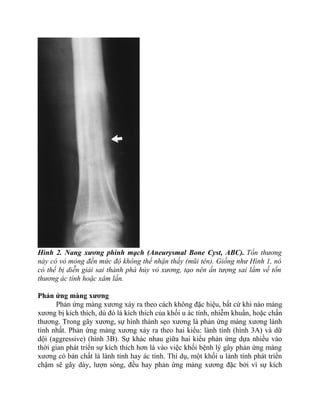

Hình 2. Nang xương phình mạch (Aneurysmal Bone Cyst, ABC). Tổn thương

này có vỏ mỏng đến mức độ không thể nhận thấy (mũi tên). Giống như Hình 1, nó

có thể bị diễn giải sai thành phá hủy vỏ xương, tạo nên ấn tượng sai lầm về tổn

thương ác tính hoặc xâm lấn.